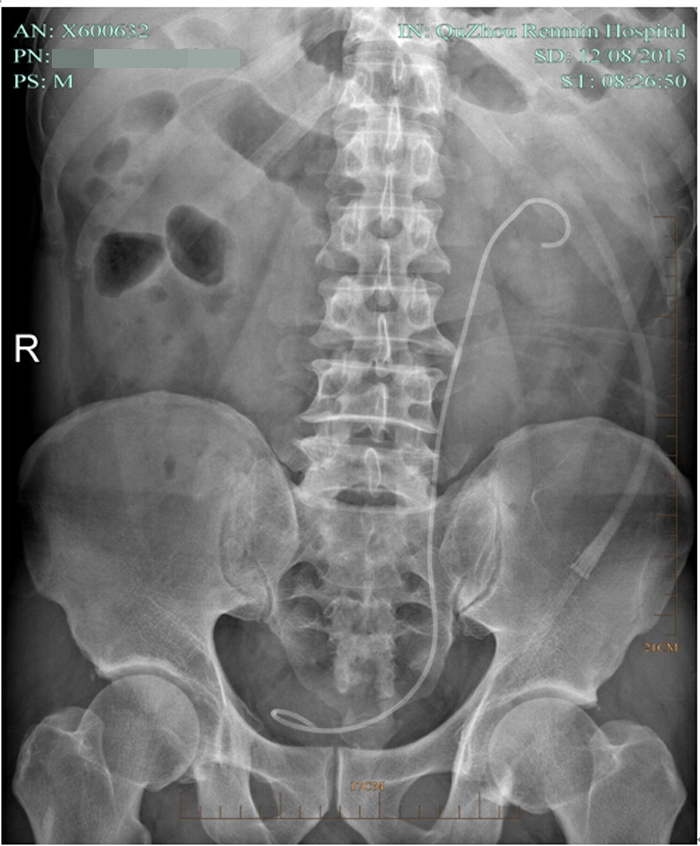

??? 術(shù)后第七天,復查泌尿系平片無結(jié)石殘留,拔了腎造瘺管出院。因為腎結(jié)石手術(shù)都需要放置輸尿管支架管,出院時護士叮囑出院后要多喝水,避免活動過多引起血尿,1個月后來拔支架管。

術(shù)后復查平片

術(shù)后復查泌尿系平片